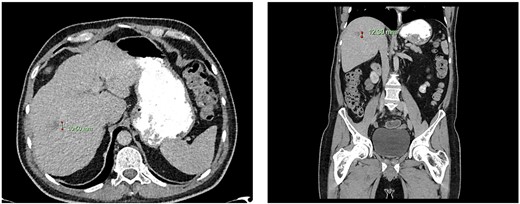

Computed tomography dated 15 January 2013 of the abdomen and pelvis measuring 10.50 mm (anterior–posterior) lesion at liver segment 5/6 in axial (left) and coronal (right) view.

Subsequent surveillance imaging including magnetic resonance imaging and CT scans demonstrated gradual reduction and eventual complete resolution of the liver metastases (refer to Figs 1–4). Furthermore, routine colonoscopy and a positron emission tomography (PET) scan revealed no evidence of locoregional cancer recurrence nor distant metastatic disease present; essentially rendering the patient cured from an initial diagnosis of metastatic rectal cancer. It has been at least a decade since his initial diagnosis and the patient remains in remission.

Following discussion within a multidisciplinary team, the patient underwent an uncomplicated palliative open Hartmann’s procedure in December 2012 for ypT3N1M1 upper rectal adenocarcinoma (1 out of 14 involved lymph nodes, immunoperoxidase staining of the tumour was negative for CK7, CK28 and CD18). Post-operatively, the patient opted for no further chemoradiotherapy and was also not deemed for surgical intervention regarding the liver metastases.